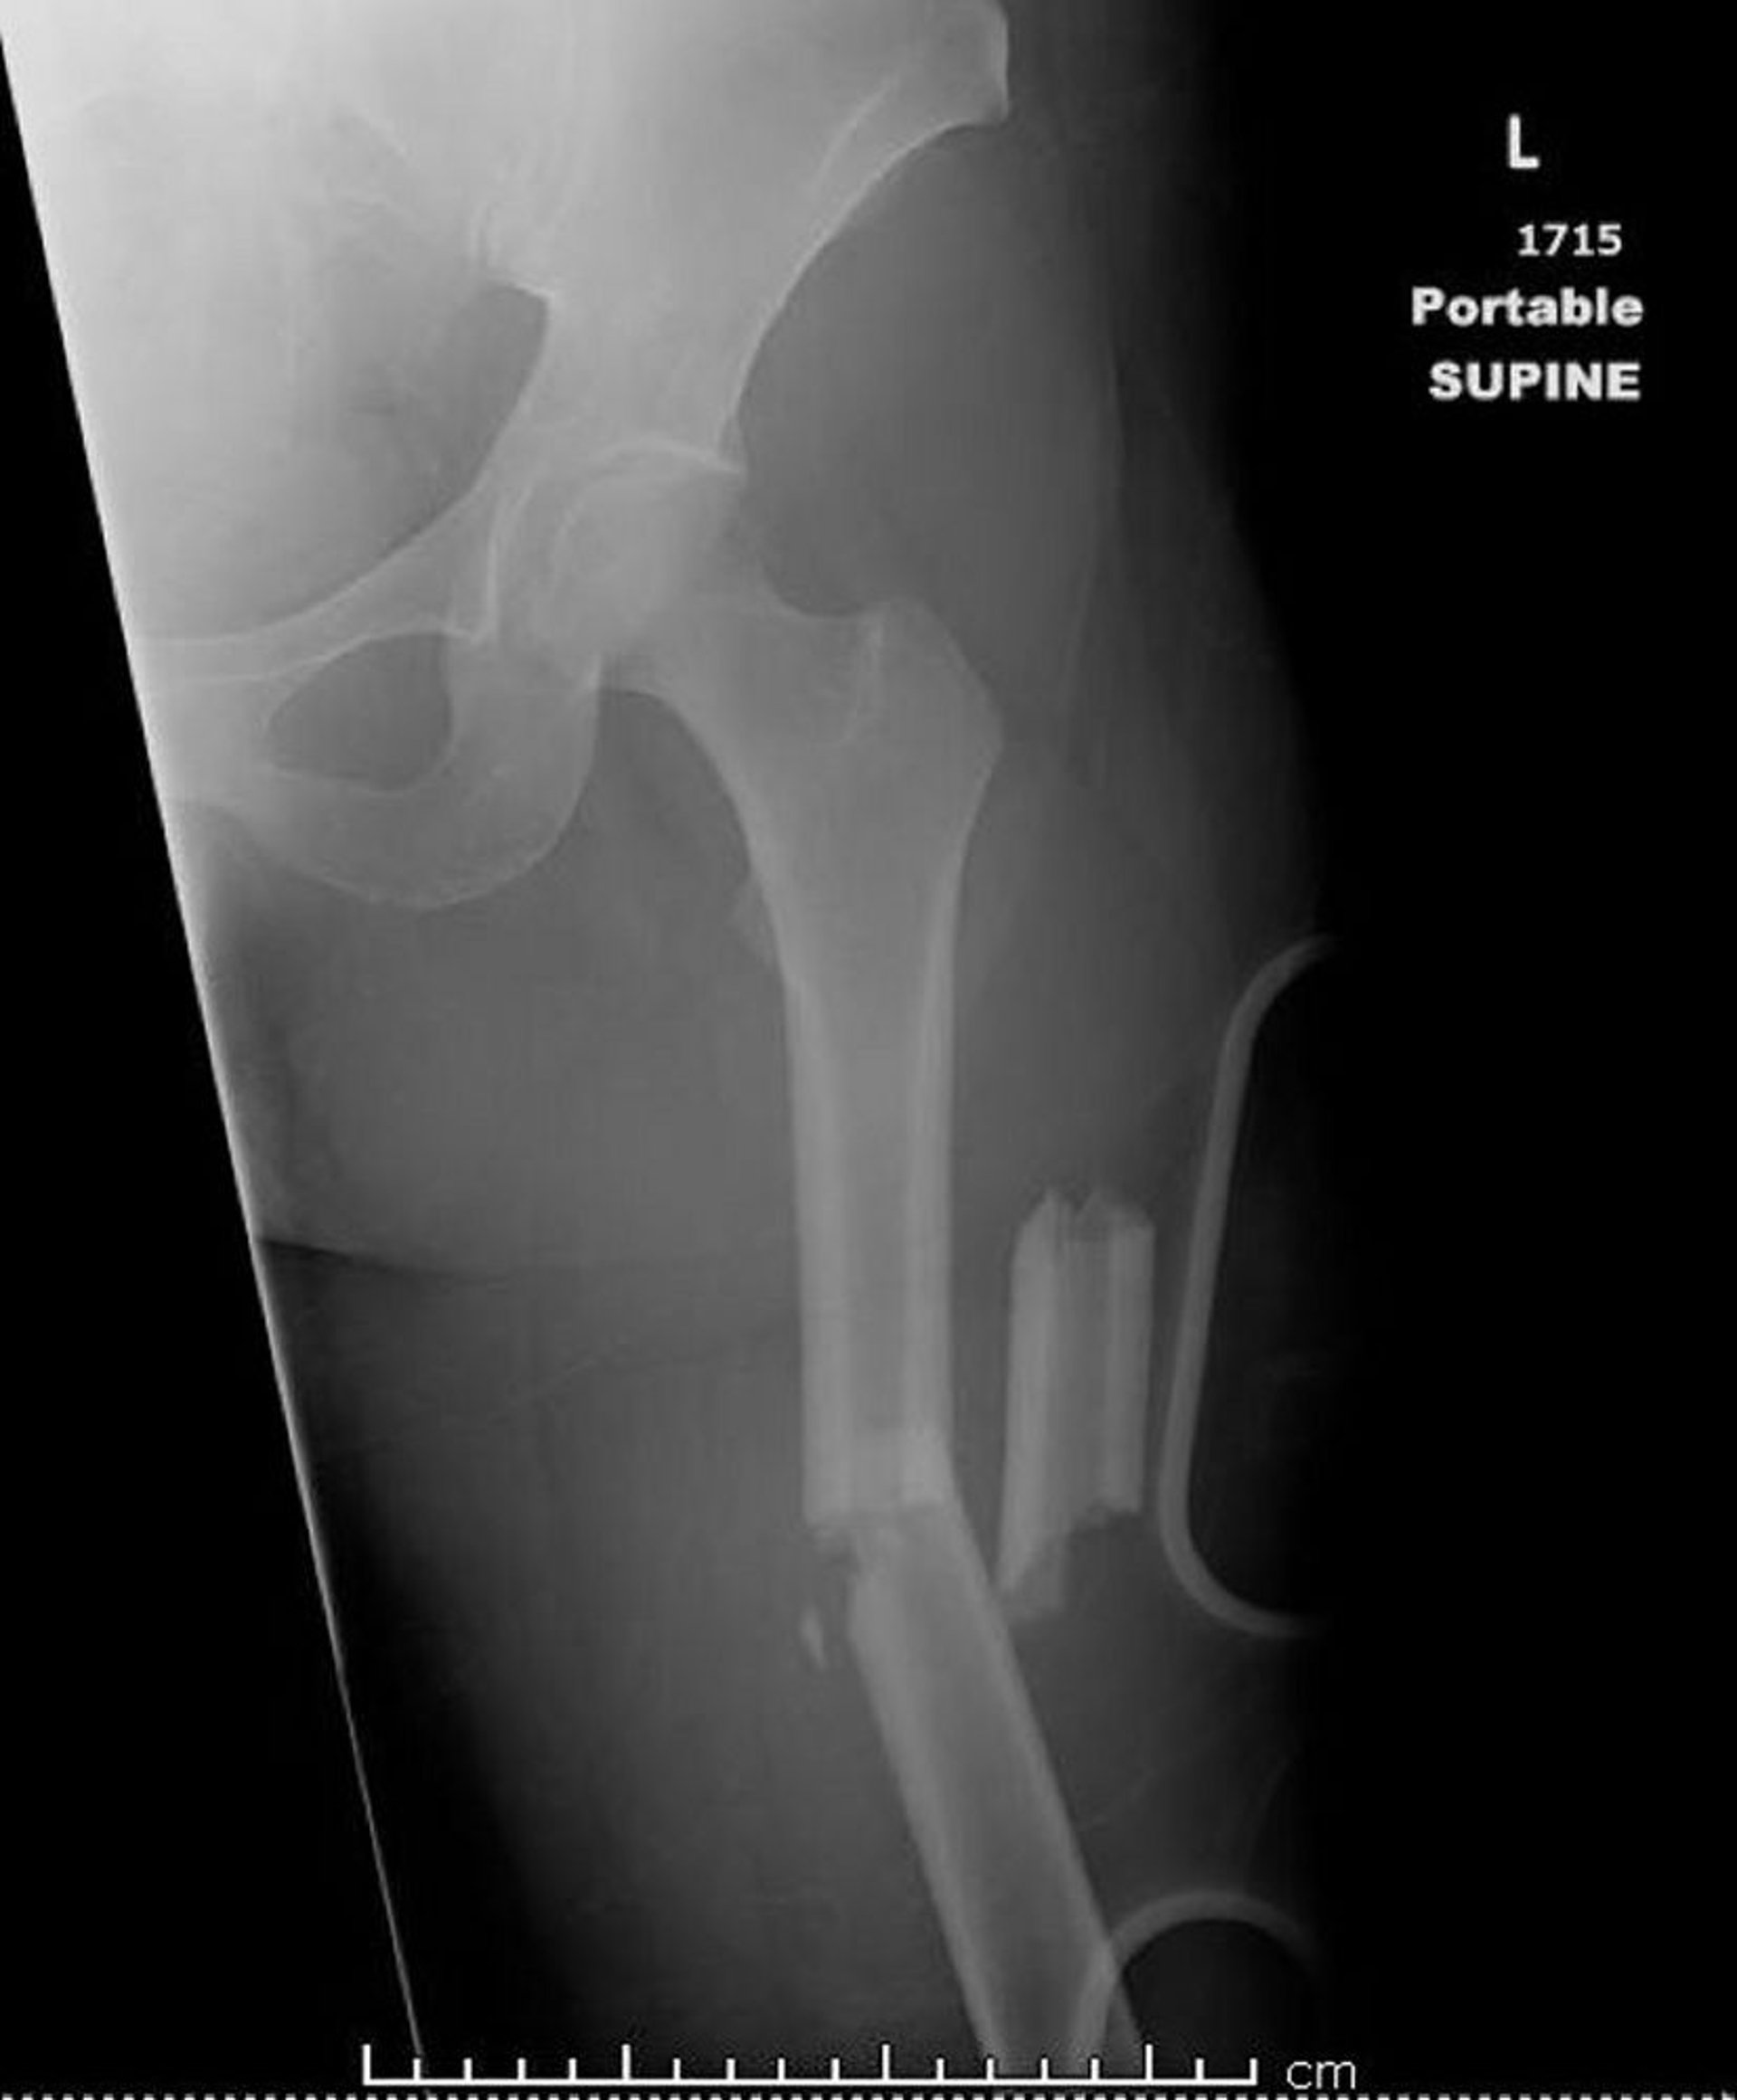

Fracture médiodiaphysaire du fémur (1)

Cette image montre une fracture fémorale mi-diaphysaire comminutive, angulée et raccourcie.

Image courtoisie de Danielle Campagne, MD.